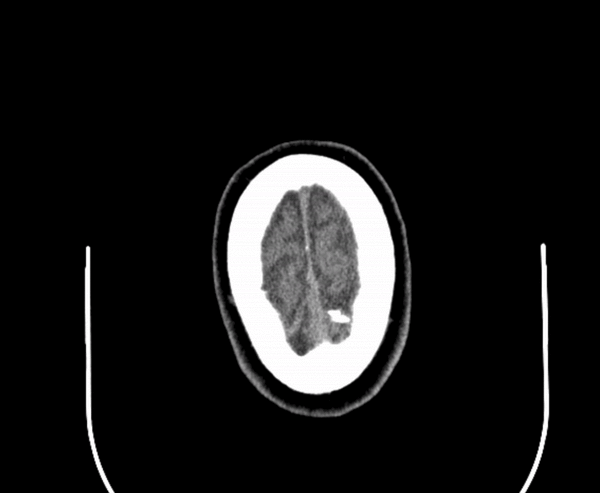

If a picture is worth 1000 words, how many words is a DICOM?

A tool for interactive case presentations